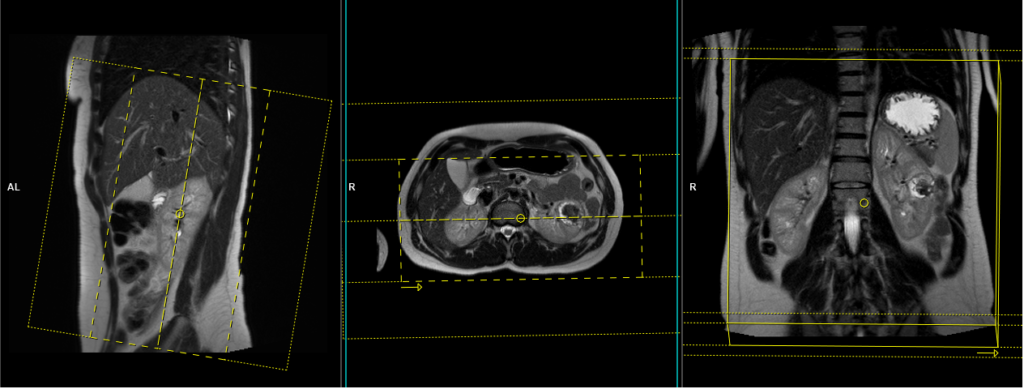

DWI epi 3 scan trace axial 3mm free breathing

Plan the axial slices on the coronal free-breathing localizer; angle the position block parallel to the right and left renal pelvis. Check the positioning block in the other two planes. An appropriate angle must be given in the sagittal plane (perpendicular to the long axis of kidney). Slices must be sufficient to cover both kidneys from two slices above the upper pole of kidneys down to two slices below the lower pole of kidney. Phase oversampling and, in the case of 3D blocks, slice oversample, must be used to avoid wrap around artefacts. Consider adding saturation bands at the top and bottom of the block to minimize artifacts caused by fat signal, arterial pulsation, and breathing.